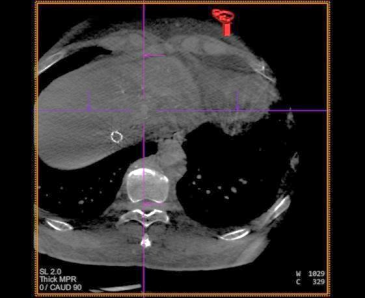

患者仰卧,右侧腹股沟区消毒铺巾,穿刺右股动脉,置入5.0Fr 导管鞘,经鞘进入 RH 导 管,在主动脉弓处成形,选择性进入腹腔干,行血管造影,肝右叶无明显肿瘤染色,肝左动 脉由胃左动脉发出,采用科睿驰医疗提供“智鹏”2.0Fr 微导管选择进入肝左动脉造影,行CBCT 扫描可见肝左内叶肿瘤强化病灶,大小约 1cm,肝左外叶病灶与胃左动脉分支共干,无法避开进一步超选择,超选择进入肝左内叶,造影明确到达把血管,选用 100-300μm“睿 渊”DiaSphere®载药微球加载 50mg 表柔比星,载药完毕后,予注入 2ml 载药微球,再 次行 CBCT 扫描,原肝左内叶病灶无强化,术中患者生命体征平稳,撤出导管,压迫止血、 包扎,患者安返病房。

术中 CBCT 可见肝左内叶肿瘤强化病灶

栓塞结束后 CBCT 扫描,原肝左内叶病灶无强化